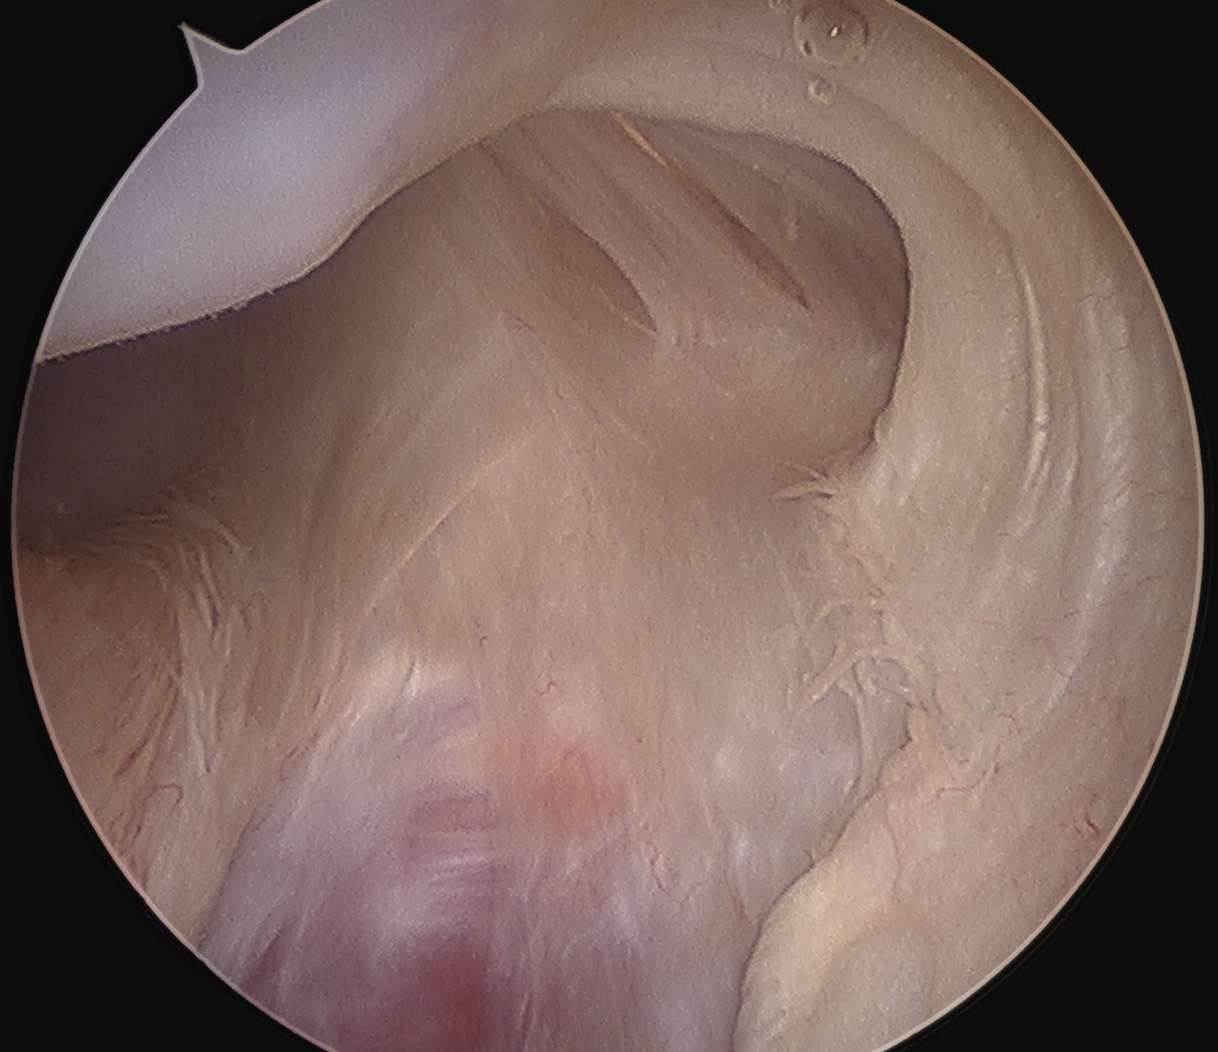

Arthroscopy

Capsule tear anteriorly, extending up into humeral insertion

Intact anterior labrum with capsular tear, axillary nerve seen below capsular tear in axillary recess